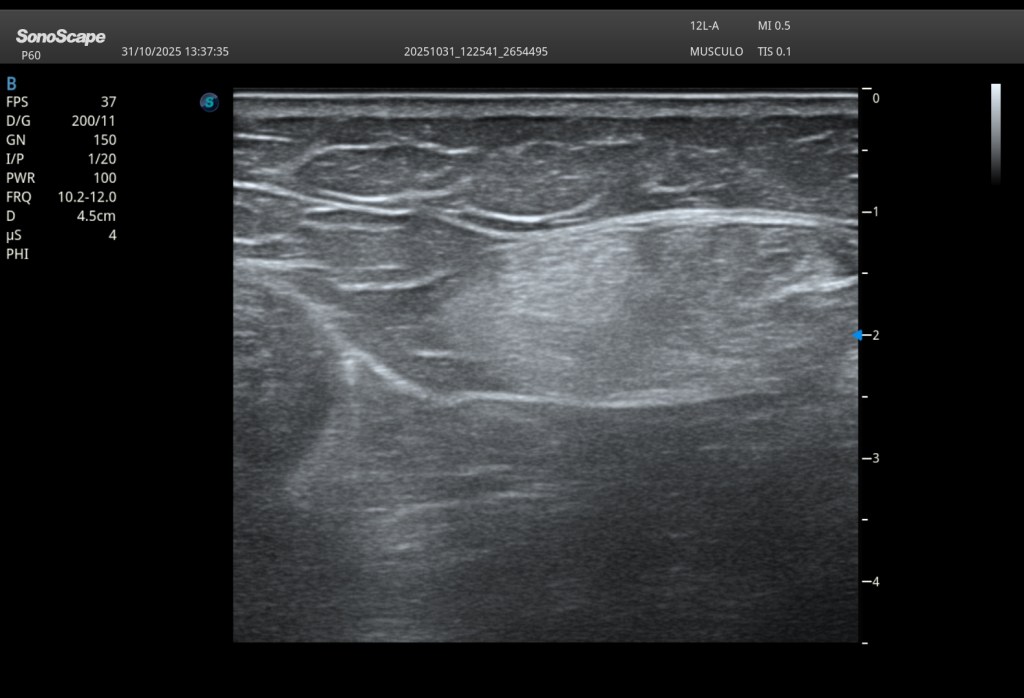

Hallazgos ecográficos

A nivel de la cabeza femoral izquierda, en la región profunda del psoas ilíaco, se identifica:

En eje longitudinal (eje largo – línea roja): Imagen anecoica alargada Localizada en las fibras profundas del psoas Con una longitud aproximada de 2,5 cm En eje transversal (eje corto – línea amarilla): La lesión se reproduce claramente, confirmando su existencia siempre en dos ejes. Si no lo veo en 2 cortes, no existe.